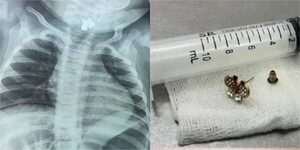

Popular / ¡Dionoguarde! Beba de diez meses tragó un arito

Una pequeña de Caacupé fue trasladada de urgencia al INERAM, donde los médicos descubrieron que la beba de apenas diez meses tragó un arito que le complicaba su estado de salud. La bebé había llegado con fiebre y una infección urinaria hasta el nosoco,... [Leer más]

Popular / ¡Bebé de 10 meses omokõ un arito y la salvaron!

Una pequeña bebé de 10 meses oriunda de Caacupé, llegó de urgencias al INERAM porque estaba con fiebre persistente, diarrea, entre otros síntomas por lo que se le solicitó una radiografía porque no mejoraba con nda, hasta que uppepe encontraron lo ines... [Leer más]